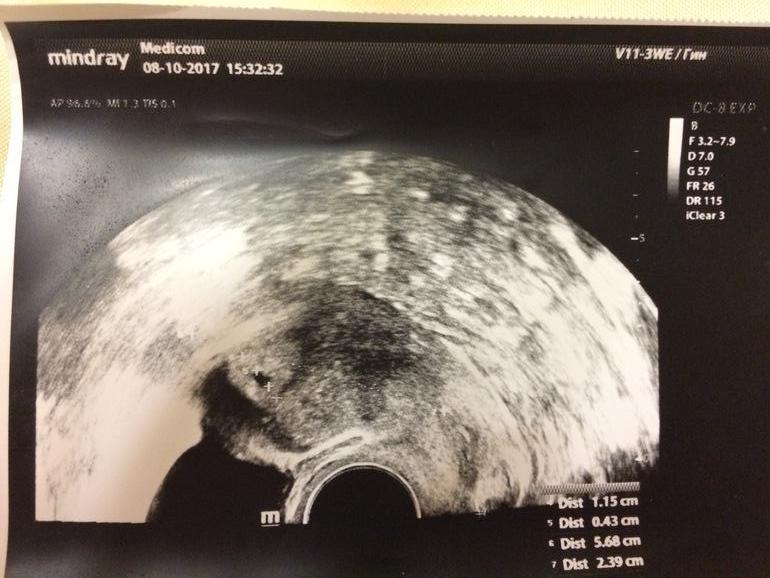

Девочки, всем привет!!Такая история, тест оказался положительным🤗🤗🤗🤗Счастья нет предела)Сходила к гинекологу , все хорошо, маточная Беременность)Последние месячные были 7 сентября...поставила акушерский срок 4 недели и 5 дней...Ну не так то чем и хорошо оказалось...Сдала хгч...И результат просто ошарашил меня.....226.8😱😱😱😱Почему так?Чем это все закончится??? ЗБ или выкид

И пусть в меня полетят кучу тапок !!! У меня при хгч 300 нашли пя в матке . Причем два раза делала узи а разных клиниках , и оба врача нашли пя .